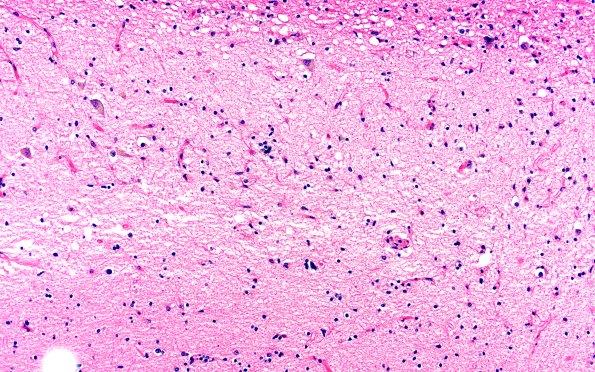

Hippocampal Sclerosis of Aging

7B5 HS no AD (A41273) H&E 20X

The epicenter of the devastation of CA1. (H&E)